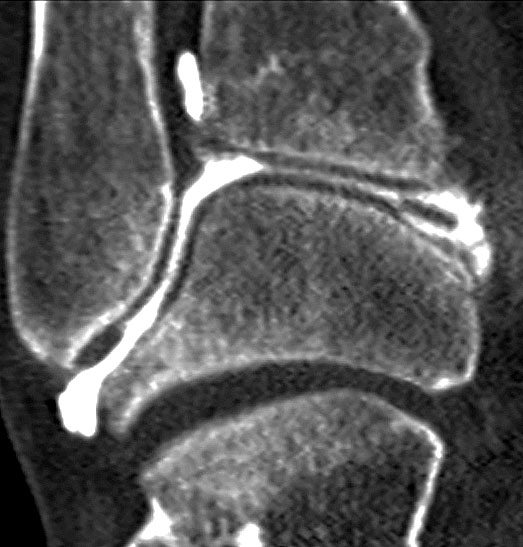

Die Computertomographie hat im Laufe der letzten Jahre eine Renaissance in der Diagnostik von chondralen und osteochondralen Läsionen am Talus erlebt. Die Verwendung von Spiral-CT´s (Abb. 7 und 8) mit der Möglichkeit multiplanarer Rekonstruktionen hat die diagnostische Qualität deutlich erhöht 18. Die Stärken zeigen sich insbesondere in der Beurteilung des subchondralen Knochens. In der Diagnostik kleiner Risse mit zystischen Veränderungen in welche Synovialflüssigkeit eindringen kann und daher klinisch bedeutsam ist, zeigt sich eine Überlegenheit gegenüber der MRT-Diagnostik 17. Die im CT abschätzbare Ausdehnung der subchondralen Zyste entspricht im Gegensatz zur MRT mit Abbildung des perifokalen Knochenmarksödems besser dem intraoperativ zu erwartenden Befund 16. Zudem ist die Untersuchungszeit kürzer im Vergleich zum MRT. Allerdings ist eine Beurteilung des Knorpels ohne die Applikation von Kontrastmittel nicht möglich. In einer Vergleichsstudie zwischen MRT und CT in der Diagnostik osteochondraler Läsionen am Talus wurde deshalb nur 81% der osteochondralen Läsionen mit der CT-Untersuchung korrekt diagnostiziert, während dies bei 96% der MRT-Untersuchungen der Fall war. Dafür wies die CT allerdings eine leicht höhere Spezifität auf (99% vs. 96%) 18. Im Vergleich zur MRT-Arthrographie besteht sogar eine höhere Interobserver Reliabilität und leicht bessere Sensitivität in der Entdeckung von Knorpelläsionen 25.